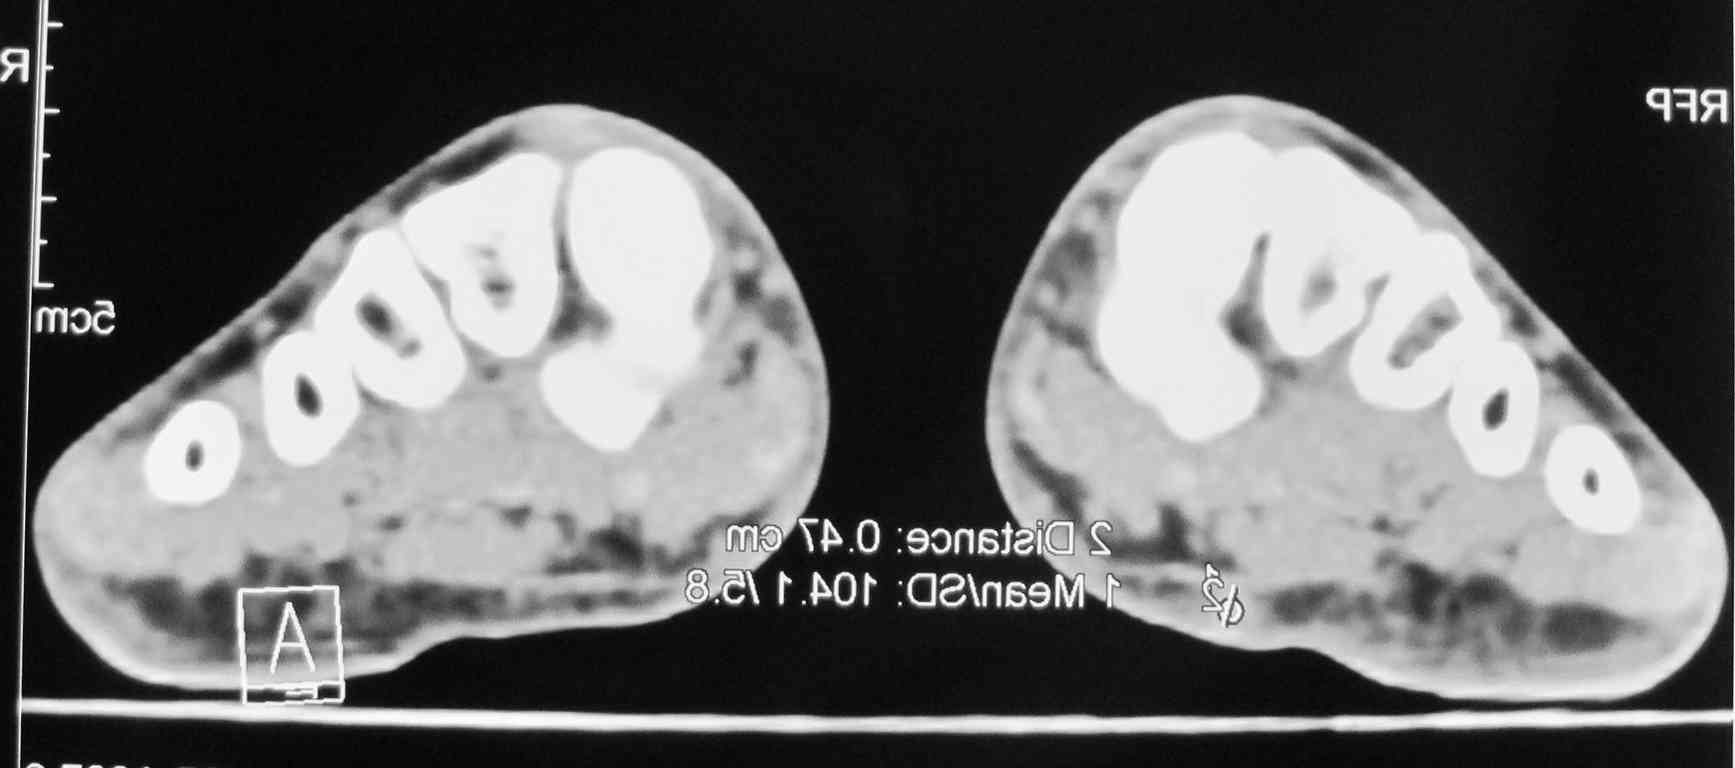

Мужчина 58 л. месяц назад наступил на камень, после того, как прошли боли, почувствовал уплотнение с медиальной стороны правой стопы.

Сделал КТ 02.11.2010 г.

Пальпаторно: определяется уплотнение размеры с горошину (0,3 Х 0,2), при пальпации безболезненно, малоподвижное. Кожные покровы в области уплотнения не изменены.

Мне по снимкам кажется, что это маленькая кальцифицированная гематома. Я бы убрал.